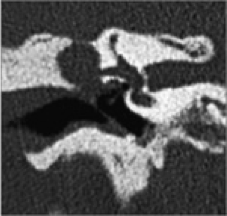

- CT scan of the temporal bone